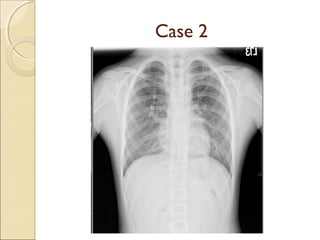

A resident in radiology presents two interesting cases: the first involves a harmatoma, and the second concerns a patient with double superior vena cava and tracheal bronchus. Both cases provide learning opportunities for radiology residents to recognize rare anatomical variations and abnormalities.